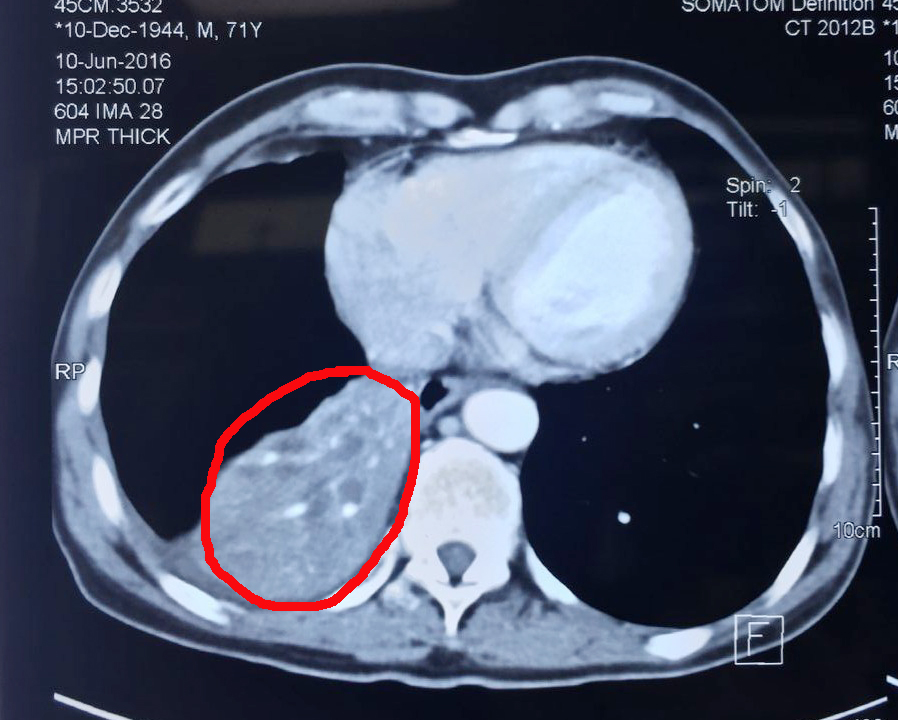

命途無常,無驚無險經(jīng)歷了大半輩子,楊清貴夫婦正忙著頤養(yǎng)天年,生活卻被種下了一顆巨大“炸彈”。2015年,楊清貴持續(xù)出現(xiàn)咳嗽、咳痰、呼吸困難10個月,吃藥也不見效果。后經(jīng)檢查發(fā)現(xiàn),楊清貴的右肺有一個約10*6cm大小的腫塊,確診為肺癌。楊清貴十分害怕,擔心自己能否好起來。“在印尼,癌癥是很可怕的,人們都覺得它是絕癥。”張英友解釋道。醫(yī)生建議楊清貴手術治療。楊清貴怕痛,拒絕了。一個星期后,楊清貴的兒媳從網(wǎng)上了解到圣丹福·廣州現(xiàn)代(腫瘤)醫(yī)院,她建議楊清貴:“爸,你到中國去吧,那里的廣州現(xiàn)代(腫瘤)醫(yī)院不用開刀。”到雅加達辦事處預約好入院時間,一周后,楊清貴來到了圣丹福·廣州現(xiàn)代(腫瘤)醫(yī)院。

腫瘤治療前